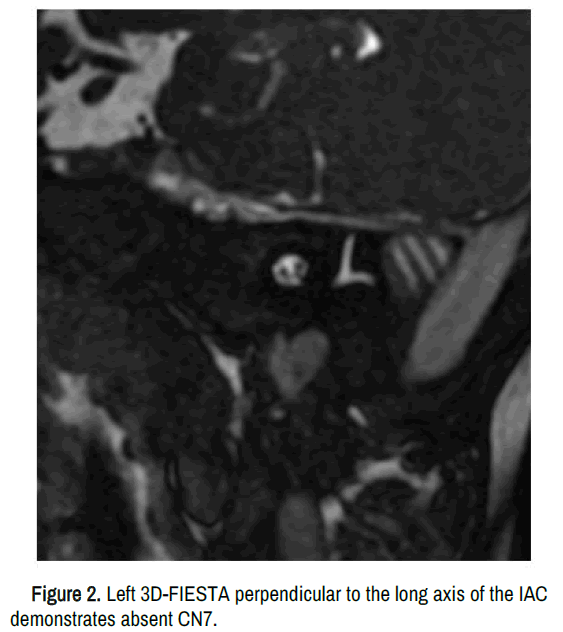

Figure 2. Left 3D-FIESTA perpendicular to the long axis of the IAC demonstrates absent CN7.

In addition to absent facial and abducens nerves, reported MRI findings include pontine and medullary hypoplasia with straightening of the floor of the fourth ventricle as a result of absence of the facial colliculus, cerebellar hypoplasia, calcification of the pons and absence of the middle cerebellar peduncles. Treatment for facial paresis involves reconstructive plastic surgery with muscle transplantation. Mobius syndrome is a rare case of aplastic or hypoplastic CN7 and CN6. It is important to identify the presence of these nerves on 3D-FIESTA in a patient with facial or abducens nerve palsy.